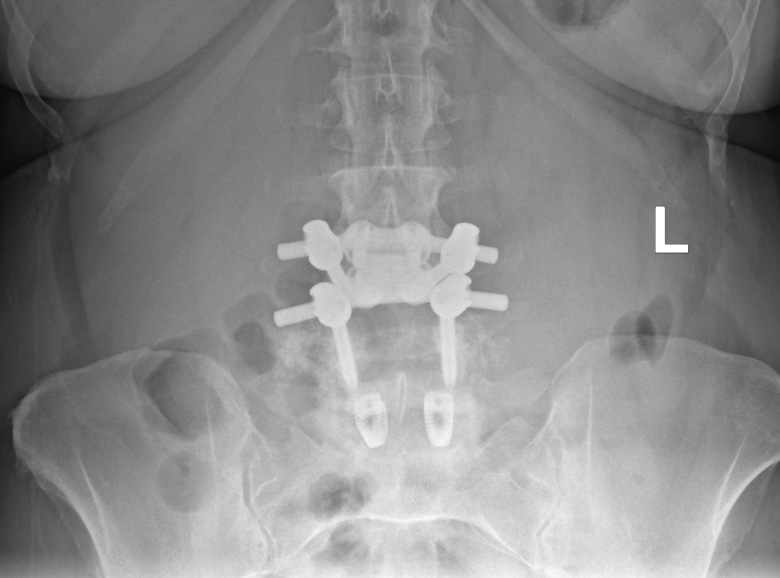

We are proud to announce that Dr. Brenton Pennicooke recently performed the very first TOPS (Total Posterior Spine) procedure within the BJC system by a WashU Medicine provider. The procedure, performed at Barnes-Jewish St. Peters Hospital, offers a motion-preserving alternative to traditional spinal fusion. This milestone represents an important step in expanding advanced spine care at WashU Medicine.

The TOPS implant works by stabilizing the spine after relieving pressure on the nerves while still allowing natural movement. Preserving motion at the treated level helps maintain normal spine mechanics and may reduce stress on adjacent segments, a common concern with fusion.